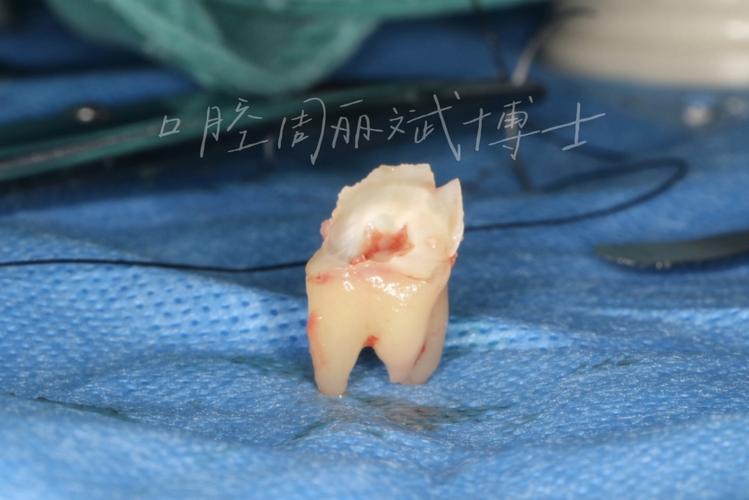

最常见的是冠周炎,智齿萌出时,牙齿可能仅部分露出牙龈,形成“盲袋”(牙龈与牙齿之间的空隙),食物残渣和细菌易堆积,当身体免疫力下降(如熬夜、感冒)时,会引发牙龈红肿、疼痛、张口受限,严重时甚至导致面部肿胀、发烧。

损害邻牙,若智齿阻生(如水平阻生、近中阻生),其萌出力量可能挤压正畸后排齐的牙齿,导致牙齿排列不齐复发,或使邻牙(第二磨牙)龋坏、牙根吸收。

第二步:评估是否需要拔除,若智齿满足以下任一情况,通常建议拔除:

- 完全阻生或部分萌出,反复引发冠周炎;

- 智齿位置不正,与邻牙间隙过小,易导致邻牙龋坏或吸收;

- 正畸后牙齿排列整齐,智齿萌出可能造成复发;

- 智齿本身龋坏或牙周病严重,无保留价值。